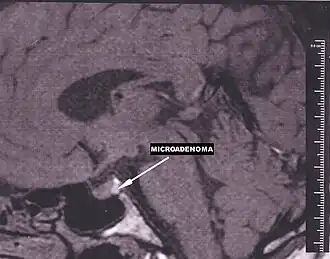

![]() Localización de la hipófisis (color rojo) en la base del cráneo. | ||